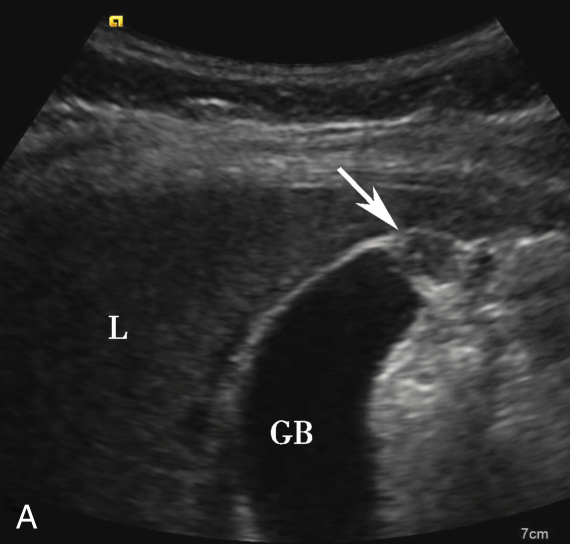

(1)局限型胆囊腺肌症:

好发于胆囊底部,灰阶超声图像通常呈边界清楚的低回声(图2-4-1A)。病变内部回声不均匀,能够观察到小片状无回声区,部分病变内可见点状高回声后伴彗星尾征(图2-4-1B)。CDFI通常无明显血流信号,部分病变内的点状高回声后方可见“快闪伪像”(图2-4-1C)。

图2-4-1 局限型胆囊腺肌症常规超声图像

A.胆囊底部低回声结节(箭头所示),边界清楚,形态规则;B.结节内可见点状高回声后伴彗星尾征(箭头所示);C.CDFI示结节内可见“快闪伪像”

GB:胆囊